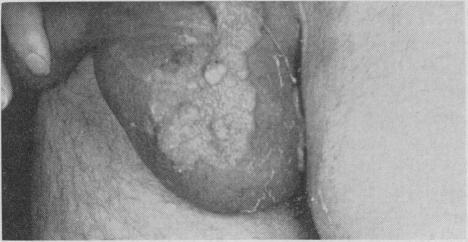

GRANDBOIS J

Can Med Assoc J. 1958 Nov 15;79(10):828-32.